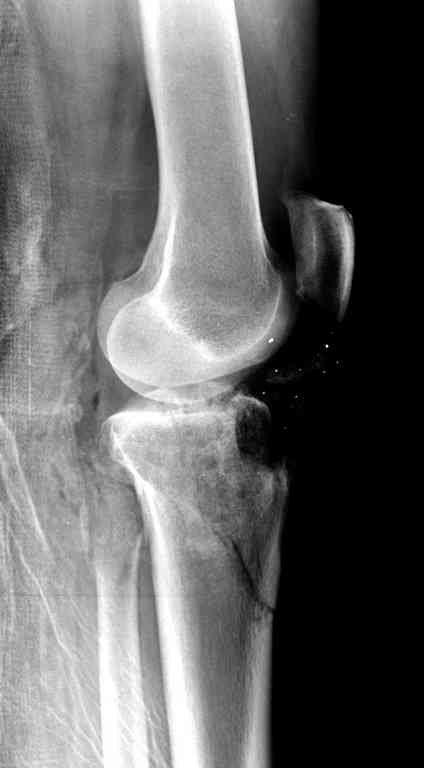

Одинокий кортикальный шуруп не удержит тибиальный бугор, сустав тибиал плато оставлен без репозиции и фиксации.

Здесь применение материала Plexur http://www.plexur.com для пластики при дефектах кости у больной с огнестрельной раной латерального тибиал плато с повреждением малоберцового нерва. Несмотря на интактный медиальный мышелок, для профилактики от вальгуса установлен АВФ и сделана ангиограмма.

После нескольких обработок и вакуумирования, поэтапно сделана фиксация тибиального бугра шурупами. И окончательную фиксацию закончили латеральной пластиной для тибиал плато и установкой пластического материала.